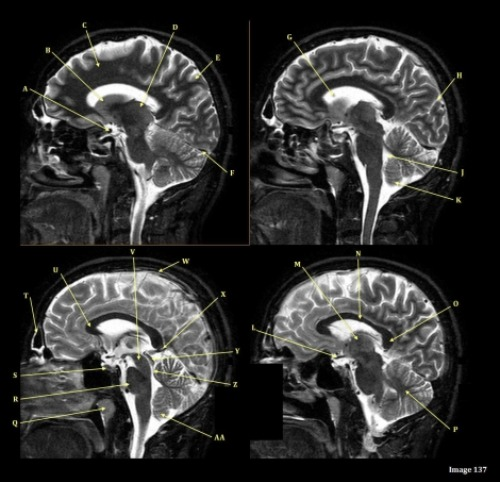

Letter R in Image 137 is pointing to:

A. Pons

B. Cerebral peduncle

C. Thalamus

D. Caudate nucleus

E. Cerebellum

F. Basal vein

Letter N in Image 137 is pointing to:

C. Genu of corpus callosum

D. Body of corpus callosum

E. Splenium of corpus callosum

Letter J in Image 137 is pointing to:

A. Aqueduct of Sylvius

B. Third ventricle

C. Sulcus

D. Fourth ventricle

E. Superior sagittal sinus

F. Lateral ventricle

Letter H in Image 137 is pointing to:

A. Grey matter

B. White matter

Letter O in Image 137 is pointing to:

Letter M in Image 137 is pointing to:

Letter X in Image 137 is pointing to:

A. Anterior frontal vein

D. Vein of galen

Letter B in Image 137 is pointing to:

Letter S in Image 137 is pointing to:

A. Optic chiasm

B. Pituitary gland

C. Inferior colliculus of midbrain

D. Internal carotid artery

E. Vein of galen

F. Straight sinus